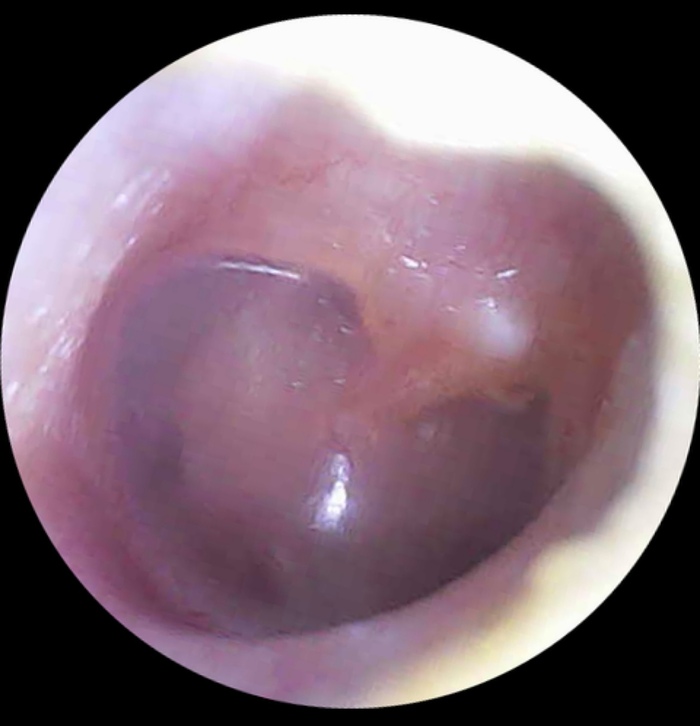

Сегодня я покажу наглядный пример, что не каждое «белое» в ухе - гной и требует антибиотиков. В качестве подопытного - мой ребенок.

При фотографировании уха видим следующую картину.

1/2

Сверху правое ухо, снизу левое. Голубой треугольник - световой конус. Отражение света камеры. При негнойных процессах он виден и имеет форму конуса. Оранжевым обозначила границу мутного отделяемого.

В ухе есть мутное отделяемое (такого же цвета сопли), но при это нет других клинических и местных признаков среднего отита.